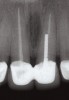

Fig 4. Initial radiograph.

Figure 4